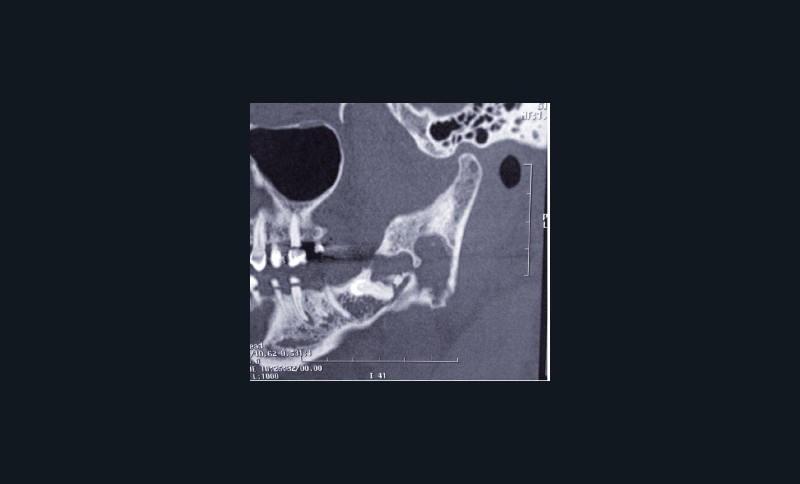

Le TDM retrouve une lésion lytique du ramus mandibulaire avec amincissement des corticales linguale et vestibulaire.